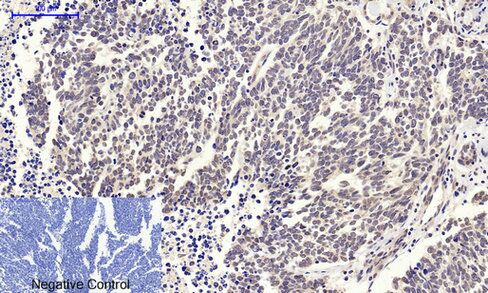

Immunohistochemical analysis of paraffin-embedded Human lung carcinoma tissue using c-Myc Polyclonal Antibody.